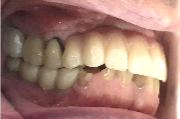

ブリッジの支台になっている奥の歯が、被せ物の中で虫歯になり、支台の役割を果たさず、前方の歯のみで支えられていました。前方の歯をそのままにして、後方の部分を切り離すと、そのまま取れてきました。中は、虫歯で歯根しか残っていない状況でした。この歯は、根管治療後、単独でオールセラミック冠を被せ、歯のないところにインプラントを埋入しました。

After